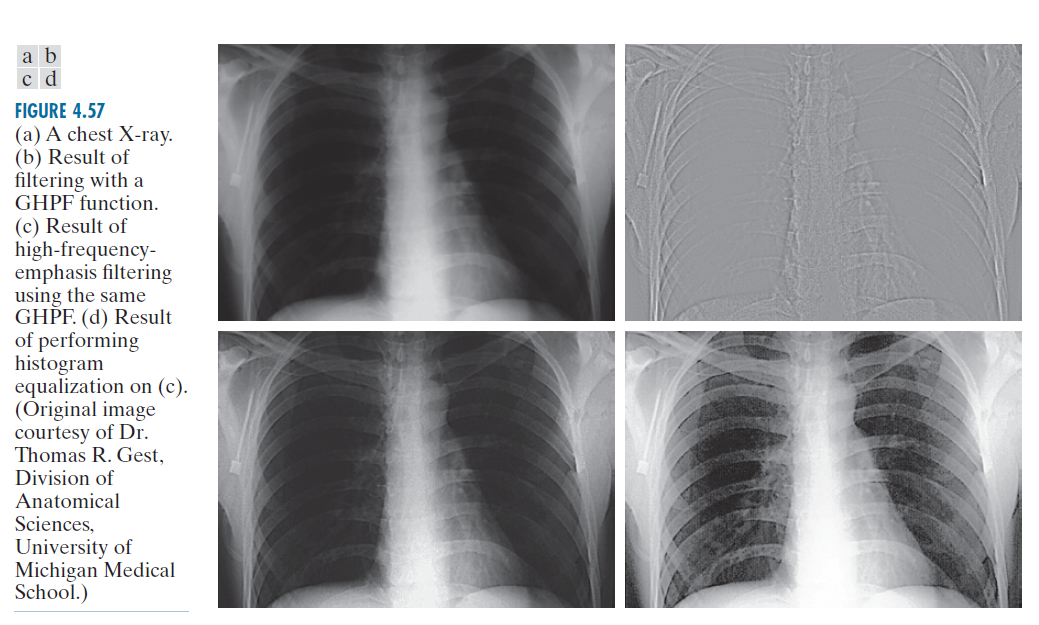

图 4.57(a) 显示了一幅 503 × 720 像素的胸部 X 光图像,其强度范围较窄。本例的目标是使用高频增强滤波来增强图像。X 光无法像光学透镜那样聚焦,因此生成的图像通常会略微模糊。由于这幅特定图像的强度偏向灰阶的暗端,我们也借此机会举例说明如何使用空域处理来补充频域滤波。

在医学图像处理中,诸如振铃效应之类的图像伪影是不可接受的,因此我们使用 Gauss高通滤波器传递函数。由于Gauss高通滤波器传递函数的空间表示也是Gauss的,因此我们知道振铃效应不会成为问题。所选的 值应提供足够的滤波来锐化边界,同时又不会过度锐化微小细节(例如噪声)。我们使用了

,大约是长图像尺寸的 10%,但其他类似的值也可以。图 4.57(b) 是对原始图像(按图 4.54 中的图像缩放)进行高通滤波的结果。正如预期的那样,图像特征相当平淡,但重要的边界(例如肋骨的边缘)清晰可见。图 4.57(c) 显示了高频强调滤波的优势,其中我们使用了公式(4-133),其中

,

。虽然图像仍然较暗,但灰度色调已得到恢复,并且特征更加清晰。

正如我们在第 3.3 节中讨论的那样,灰度级分布在较窄范围内的图像是直方图均衡化的理想选择。如图 4.57(d) 所示,这确实是一种进一步增强图像的合适方法。请注意骨骼结构和其他细节的清晰度,而这些细节在其他三幅图像中根本无法看到。最终的增强图像略有噪点,但这是 X 射线图像在灰度扩展时的典型特征。高频增强和直方图均衡化相结合的效果优于单独使用其中任何一种方法的效果。

-----------------图 4.57:(a) 胸部 X 光片。(b) 使用 GHPF 函数滤波的结果。(c) 使用相同 GHPF 函数进行高频增强滤波的结果。(d) 对 (c) 图像进行直方图均衡化的结果。(原始图像由密歇根大学医学院解剖科学系 Thomas R. Gest 博士提供。)----------